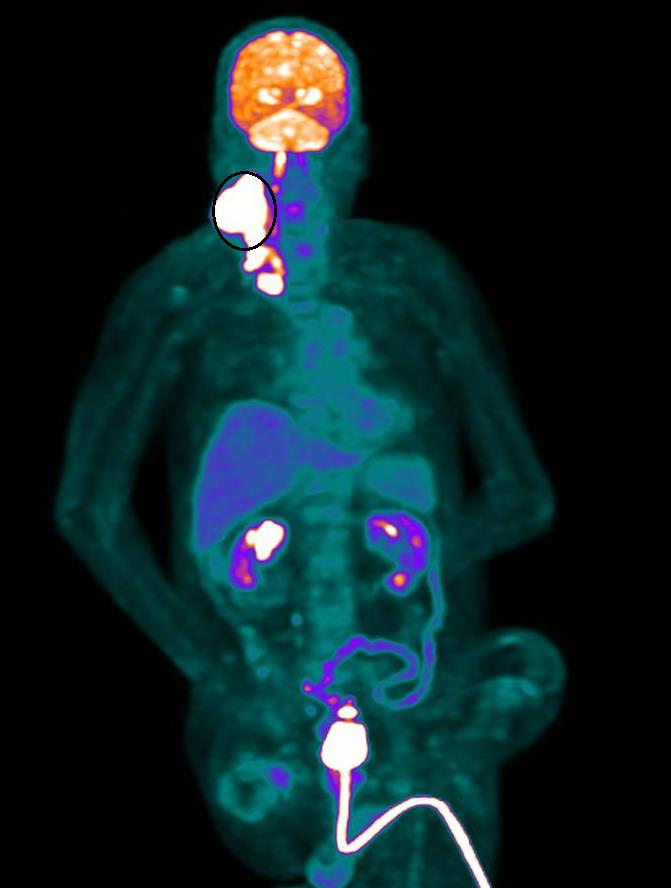

经过医疗团队分析林男身体状况虚弱,若采用化学治疗恐难以承受副作用且风险极高,经过多次深入沟通与反复讨论治疗目标、生活品质与现实条件,医疗团队与家属达成在兼顾安全的前提下,采单纯放射线治疗的共识,接下来林男接受两个月合计35次俗称「电疗」的放射线治疗,肿瘤从10公分缩小到1公分。